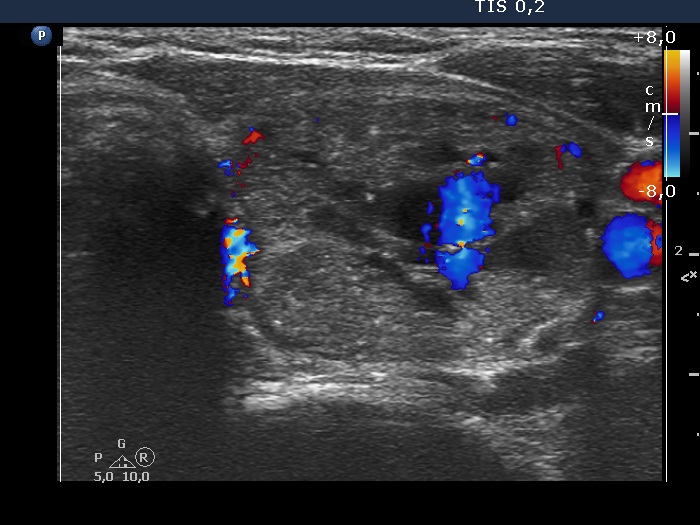

The composition of the nodule - case 6 (ultrasonographic picture 10)

Left lobe, transverse scan, color Doppler mode - - after the removal of 8 ml bloody cystic fluid. The central blue area corresponds to the blood just refilling the cystic chambers.